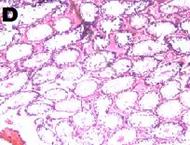

Histoarchitecture of the testes of treated animals showed mild to moderate atrophy and altered spermatogenesis (fig. 5). These were characterized by a reduction in the size of the seminiferous tubules and a decreased number of interstitial cells accompanied by spermatogenic arrest at high doses of the extract (fig. 5). The observations were in agreement with the reduced sperm numbers recorded.

Fig. 5: Photomicrograph (x40) showing histopathological profile of the testes of rat after 14 d treatment with varying doses of Carica papaya. A, B, C, D, E are control 10, 100, 300, 500 mg/kg of aqueous leaf extract of C. papaya respectively